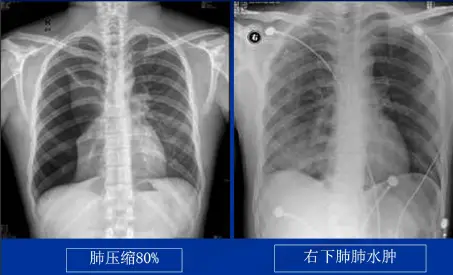

复张性肺水肿

指在气、液胸患者大量排气、排液之后,肺迅速复张后所发生的肺水肿(64%病人发生在第1小时内)。

发生的部位:一般是单侧,复张后肺水肿出现的越早,发生的越急,出现双侧肺水肿的几率就越高。